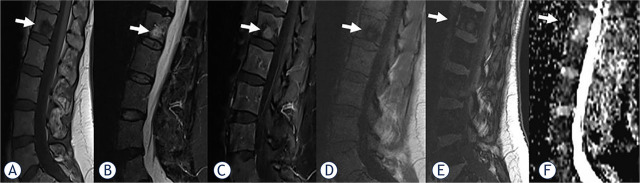

背景:分析化学位移成像(CSI)和弥散加权成像(DWI)这两种非标准磁共振成像(MRI)技术在区分恶性和良性椎体骨髓病变(VBMLs)中的作用:2020年1月至2023年12月期间,使用1.5 T系统对102名肿瘤患者进行了常规脊柱核磁共振成像,随后进行了CSI和DWI成像。从确定的 325 个 VBML 中选出 102 个有代表性的病灶(每个患者一个)。根据组织病理学或成像随访结果,VBML 被分为恶性(n = 74)和良性(n = 28)。VBMLs的定量评估参数为CSI得出的信号强度比(SIR)和DWI得出的表观弥散系数(ADC):结果:与良性 VBMLs 相比,恶性 VBMLs 的 SIR 值明显更高(P < 0.05),ADC 值更低(P < 0.05)。SIR的曲线下面积(AUC)为0.953(p < 0.001),ADC的曲线下面积(AUC)为0.894(p < 0.001)(临界值分别为> 0.82和≤ 1.57x10-3 mm2/s)。SIR 的灵敏度和特异度分别为 93.6% 和 88.5%,而 ADC 的灵敏度和特异度分别为 88.2% 和 92.3%。联合使用 SIR 和 ADC 提高了诊断准确性,其 AUC 为 0.988(P < 0.001,临界值 > 0.19),灵敏度和特异性分别为 100.0% 和 90.9%:由 CSI 和 DWI 这两种非标准磁共振成像技术得出的定量参数 SIR 和 ADC 在区分恶性和良性 VBML 方面显示出了诊断优势。在临床实践中,结合这两种方法可进一步提高脊柱磁共振成像的诊断性能和准确性。

Patients and methods: Conventional spine MRI protocol, followed by CSI and DWI was performed with a 1.5 T system on 102 oncologic patients between January 2020 and December 2023. From the identified 325 VBMLs, 102 representative lesions (one per patient) were selected. VBMLs were divided into malignant (n = 74) and benign (n = 28) based on histopathology, or imaging follow-up. The quantitative parameters for VBMLs assessment were signal intensity ratio (SIR) derived from CSI and apparent diffusion coefficient (ADC) derived from DWI.

Results: The malignant VBMLs had significantly higher SIR values (p < 0.05) and lower ADC values compared to benign VBMLs (p < 0.05). The area under the curve (AUC) was 0.953 (p < 0.001) for SIR, and 0.894 for ADC (p < 0.001) (cut-off at > 0.82, and ≤ 1.57x10-3 mm2/s, respectively). The sensitivity and specificity for SIR were 93.6%, and 88.5%, while for ADC were 88.2% and 92.3% (respectively). The combined use of SIR and ADC improved the diagnostic accuracy to AUC of 0.988 (p < 0.001, cut-off at > 0.19), sensitivity, and specificity of 100.0% and 90.9% (respectively).